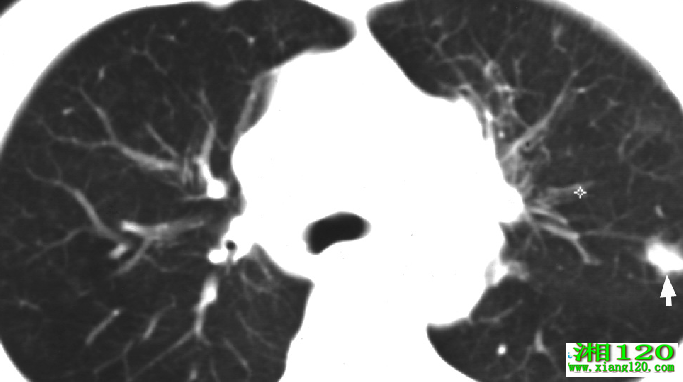

按病理学上的分类可分为小细胞与非小细胞肺癌。小细胞肺癌多认为来源于神经脊的胚胎细胞,然后移行到肺,也可至全身。相对于小细胞肺癌,其他的肺癌如、大细胞癌、腺和腺癌等统称为非小细胞肺癌。